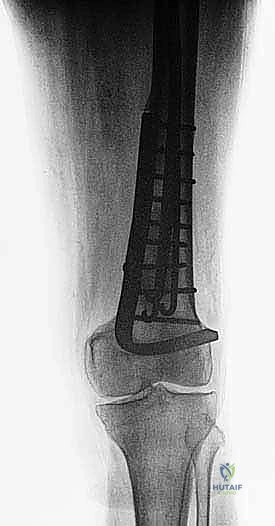

نقائل العظم الفخذي هي أورام ثانوية تنتشر إلى عظم الفخذ، مسببة الألم والكسور. يشمل علاجها الجراحي استعادة الوظيفة وتخفيف الألم من خلال التجريف والتثبيت بمسامير نخاعية أو الاستئصال وإعادة البناء بأطراف صناعية، ويتم ذلك على يد خبراء مثل الأستاذ الدكتور محمد هطيف في صنعاء.

الخلاصة الطبية السريعة: نقائل العظم الفخذي هي أورام ثانوية تنتشر إلى عظم الفخذ قادمة من أورام أولية (مثل الثدي، البروستاتا، الرئة، الكلى، أو الغدة الدرقية)، مسببة الألم المبرح والكسور المرضية التي تقعد المريض عن الحركة. يشمل العلاج الجراحي المتقدم استعادة الوظيفة، الحفاظ على استقلالية المريض، وتخفيف الألم بشكل جذري من خلال تقنيات مثل التجريف والتثبيت بمسامير نخاعية مع الأسمنت العظمي، أو الاستئصال الواسع للورم وإعادة البناء بأطراف صناعية كبرى (Megaprosthesis). يتم إجراء هذه الجراحات المعقدة بأعلى نسب النجاح على يد خبراء جراحة العظام والأورام، وعلى رأسهم الأستاذ الدكتور محمد هطيف في العاصمة اليمنية صنعاء، والذي يجمع بين الخبرة الأكاديمية والمهارة الجراحية الدقيقة.

هذا الجزء يتسع ليشكل اللقمتين الفخذيتين (Condyles) اللتين تتمفصلان مع عظم الظنبوب (القصبة) لتكوين مفصل الركبة. النقائل في هذه المنطقة تؤثر بشكل مباشر على ميكانيكا الركبة وتسبب آلاماً شديدة عند ثني أو فرد الساق. الجراحة هنا تتطلب دقة متناهية للحفاظ على أربطة الركبة (الصليبية والجانبية) أو استبدال المفصل بالكامل بمفصل صناعي للأورام إذا كان التدمير العظمي واسعاً.